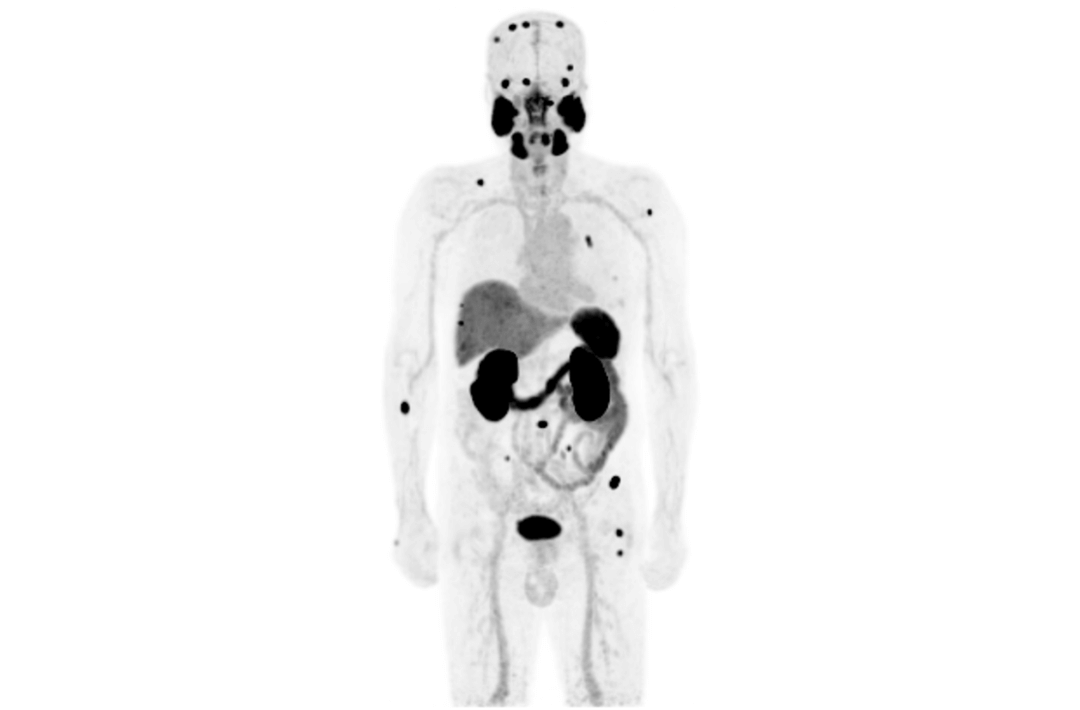

The TNM staging system is currently the most widely used staging system in the world. It can provide relevant information about the location, involvement and spread of the primary tumor through imagological examination methods. It's one of the most important examination methods to determine cancer staging. Integrated PET/MR perfectly combines molecular functions and structural images and serves as a vital means for the clinical diagnosis of tumors, cardiovascular disease, neurological disease, pediatric disease, and inflammatory disease.

However, since the launch of integrated PET/MR more than ten years ago, there have been limitations on scan efficiency. The short AFOV of PET fails to meet the needs of whole-body imaging, so it's been necessary to scan patients over multiple bed positions, which increases the scan time and reduces patient throughput.

Compared with the conventional PET system with AFOV ranging between 20cm and 25cm, the 32cm long AFOV not only improves the sensitivity of the system, but also basically covers main organs of the whole body and the regional lymphatic system where metastasis may occur, and makes it possible to realize cancer TN staging in one bed position.

In August 2019, Peking Cancer Hospital introduced United Imaging Healthcare's integrated PET/MR to make an in-depth exploration and optimization of cancer TNM staging under long AFOV. More than 500 examples of scanning various organs proved that long AFOV PET/MR could greatly increase the scan range over one bed position and improve the efficiency of cancer TNM staging.

The following are the cases of optimized TNM staging of breast cancer, esophageal cancer, prostate cancer and other diseases under the long axial field of "spatio-temporal integration" ULTRA-clear TOF PET/MR.  Thanks to Capital Medical University Xuanwu Medical Treatment for providing the image.